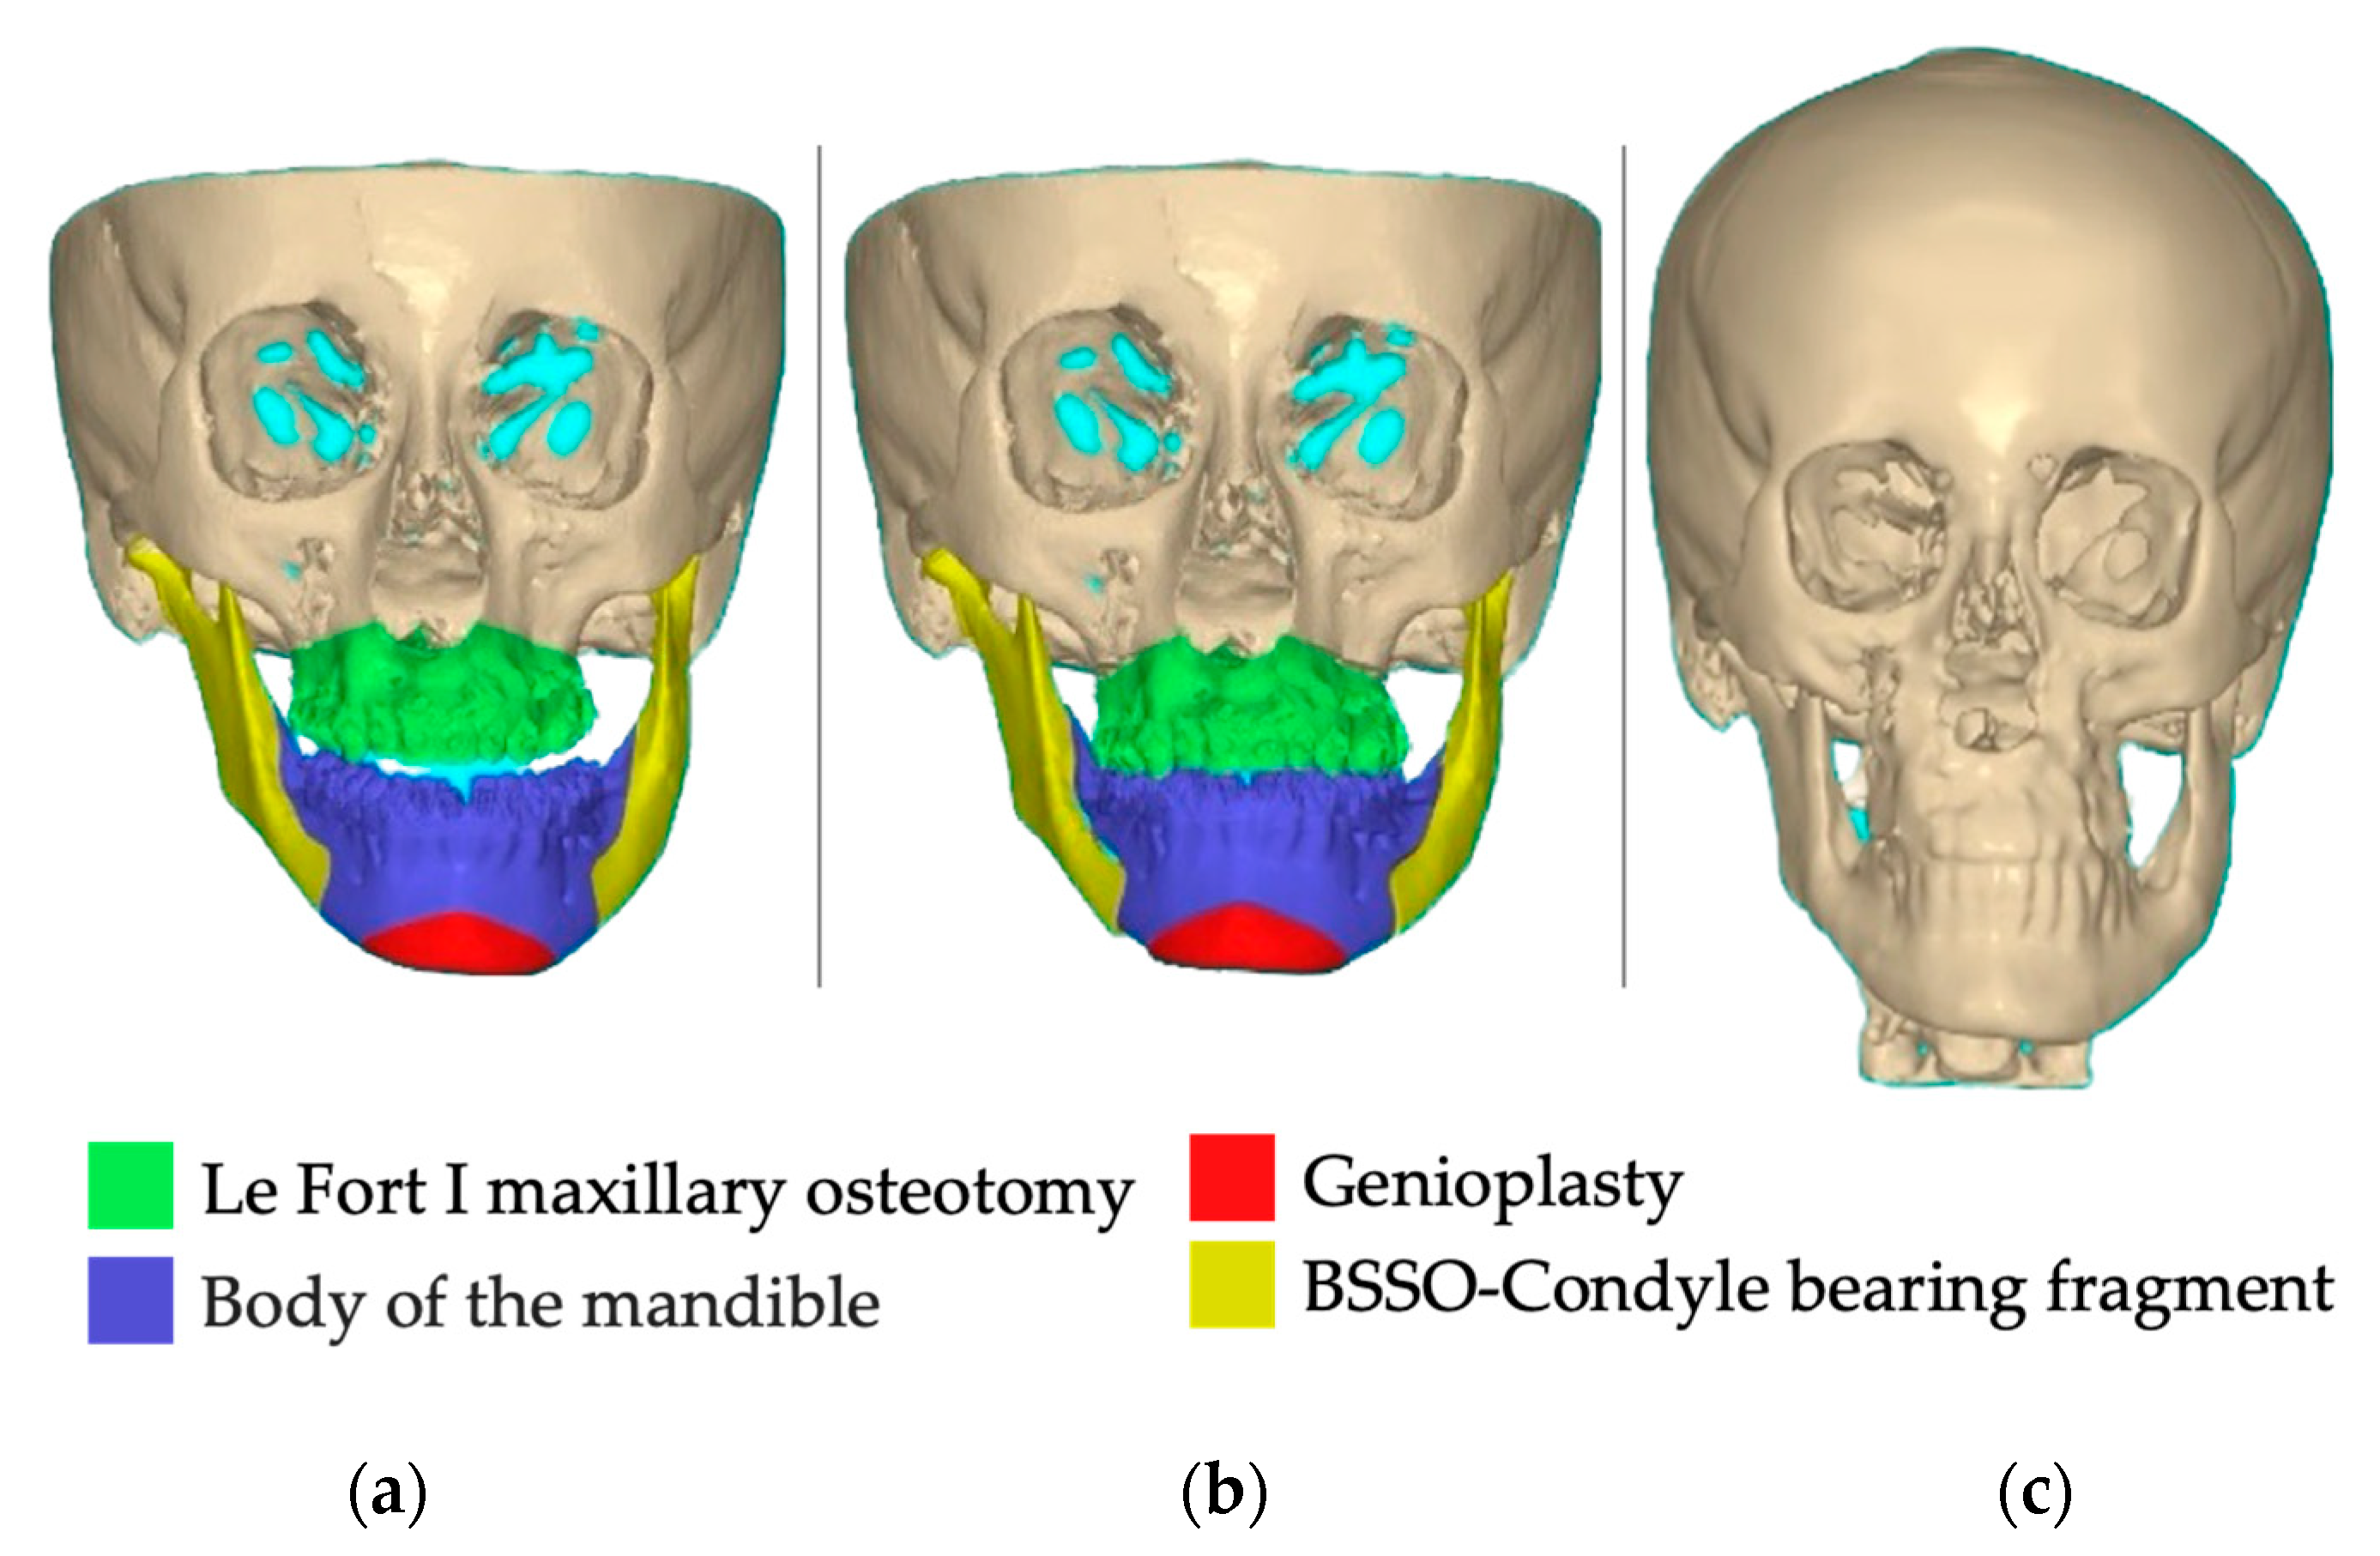

2. Case Report